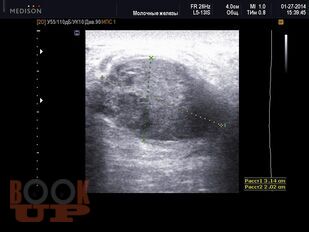

Методические аспекты ультразвукового исследования злокачественных образований молочной железы

В учебном пособии представлены методические подходы к ультразвуковому исследованию молочных желез, определены возможности ультразвукового метода исследования в выявлении и дифференциации вида злокачественных образований молочных желез, проведена оценка его роли и места в диагностическом алгоритме на основании изучения литературных данных и собственных наблюдений.